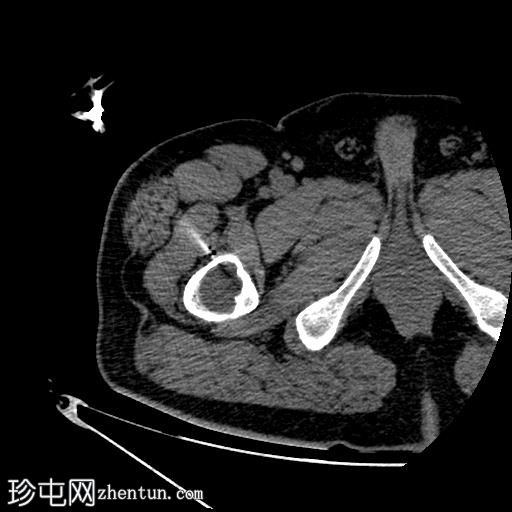

4.jpg

轴位

平扫

行CT引导下病变穿刺活检,术中及术后均未见并发症。

将活检针置于右股骨近端干骺端溶骨性透亮肿块中心后,从囊性病变中抽取血液。穿刺活检结果为阴性,未见骨髓浸润。因此,囊性病变的血液样本被送检进行组织病理学检查,结果显示无恶性肿瘤

根据CT影像学表现和组织病理学结果,应考虑右股骨干近端良性囊性骨病变。